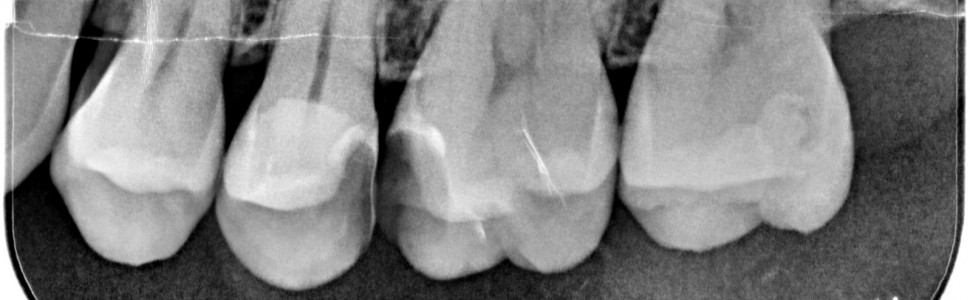

Zabieg amputacji miazgi należy do metod leczenia biologicznego i polega na odcięciu miazgi komorowej, a następnie przykryciu miazgi kanałowej materiałem bioaktywnym. Procedurę wykonuje się standardowo w zębach mlecznych i stałych niedojrzałych, jednak, jak wskazują badania, można ją z powodzeniem wykonywać w zębach stałych z zakończonym rozwojem. W pracy przedstawiono przypadek kliniczny prezentujący zabieg amputacji całkowitej miazgi w zębie dojrzałym 25 z zastosowaniem preparatu Biodentine (Septodont), który zakończył się sukcesem terapeutycznym. Wszystkie dolegliwości bólowe pacjenta ustąpiły, ząb zachował żywotność, a na tomografii można zaobserwować wytworzenie mostu zębinowego. Zabieg amputacji wpisuje się we współczesny trend minimalnie inwazyjnej stomatologii.